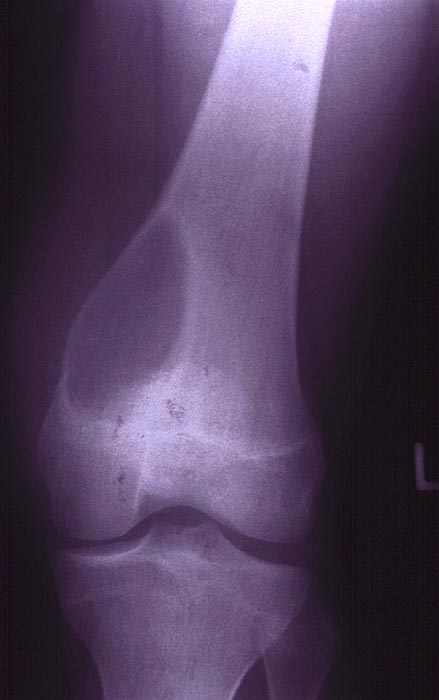

Aneurysmatische Knochenzyste

Knochen, Femur

Radiologisch erkennt man in der distalen linken Femurmetaphyse medial eine exzentrisch gelegene Osteolysezone, die mediodorsal zu einer schalenartigen Ausbeulung des Knochens mit Bildung einer Neokortikalis geführt hat. Besonders nach dorsal ist die Neokortikalis sehr dünn.